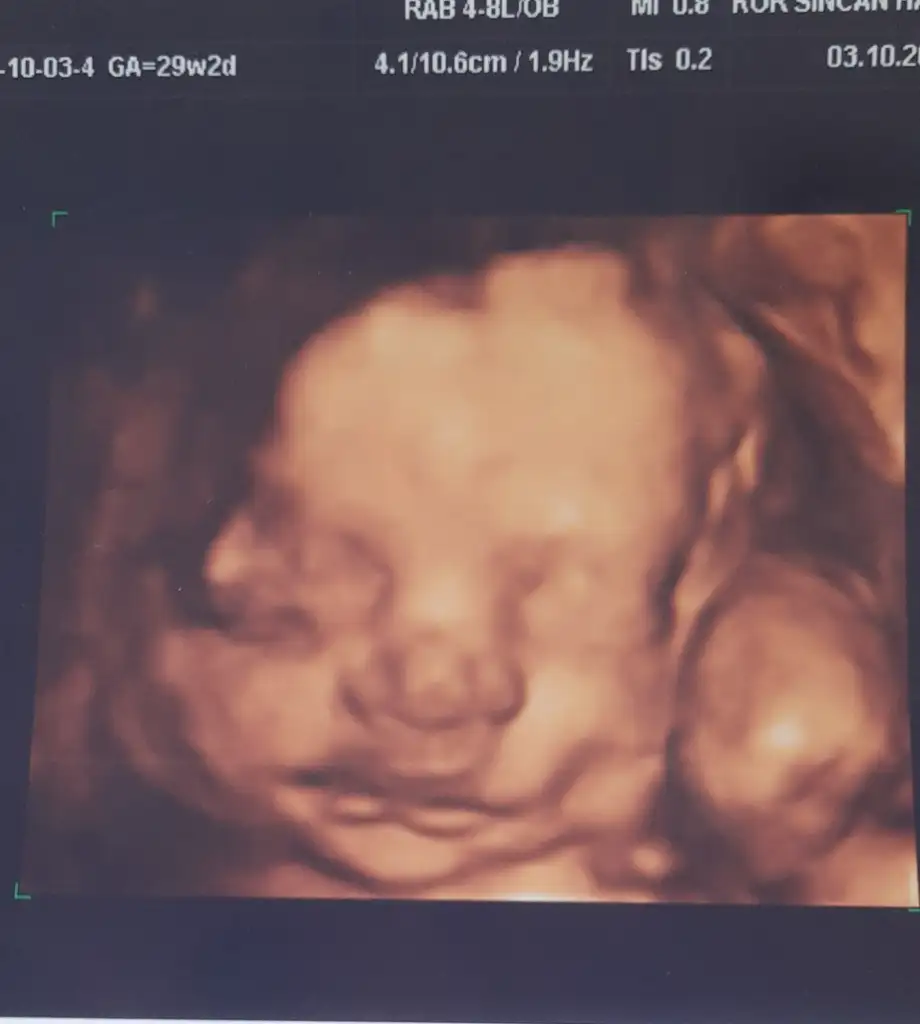

sanırım bebişim büyüyor ve levemiri arttırır belki. Pazartesi bakacağız duruma göre